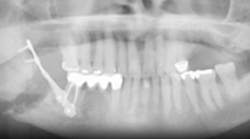

According to the National Institutes of Health (NIH), osteonecrosis is a disease where new bone does not replace old, resorbing bone quickly enough. The cause is attributed to less flow of blood to the affected area. (1) Osteonecrosis can occur in any bone, but we will discuss osteonecrosis of the jaw (ONJ).

ONJ seemed to surface about 2003, and the mechanisms surrounding it are somewhat unclear. According to researchers at University of California, Los Angeles (UCLA), we need further research about how ONJ develops and advances at a cellular level in order to develop preventive measures and interventions against it. (4) Drugs that may cause ONJ inhibit the action of osteoclasts (i.e., the cells that break down bone). It is suspected that this activity goes awry and causes ONJ, but researchers are not sure of the exact manner this works. The recent publication of the UCLA animal study concludes that drugs like bisphosphonates interfere with osteoclasts bone-resorbing functions, and suppress woven bone formation after dental trauma. This may be a possible explanation of their link to ONJ. (4)

ONJ is also linked to drugs like denosumab (Prolia), an injection drug used to treat osteoporosis, but no causal relationship has been established. (5) Bisphosphonates and denosumab reduce the rate of bone turnover and possibly decrease the effectiveness of the body’s resistance to infection. (6) Researchers of one study conclude that infection should be viewed more critically in ONJ, and that “ONJ with infection at the epicenter could justify temporary discontinuation of the ‘offending drug’ to allow recovery of macrophage production and function.” (6) Traumatic procedures should be minimized or eliminated, and harmful pathogens should be prevented from reaching the bone surface by optimal hygiene procedures. (6)